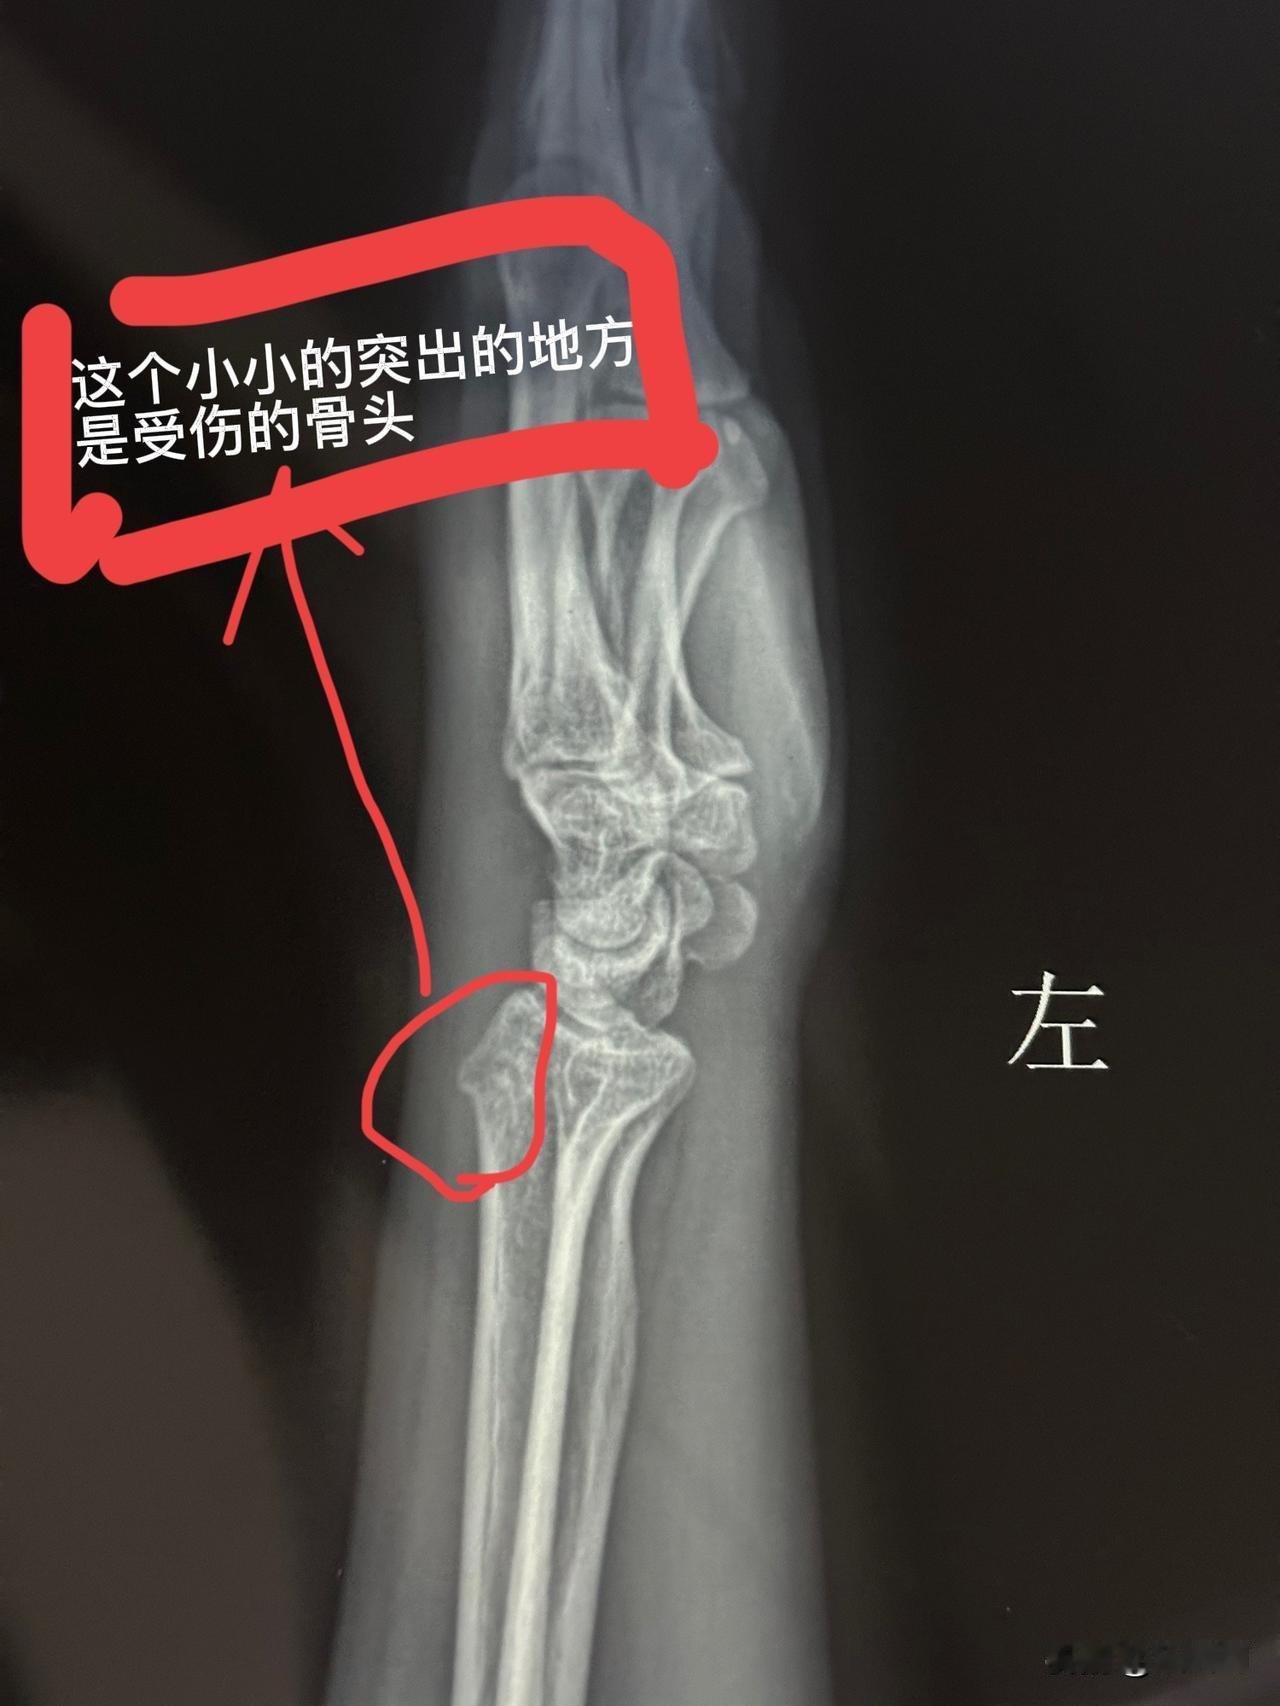

千万要接受教训! 年龄大点的人一定要注意了 懒就懒些,不要太勤快 上周三上午我在家晾衣服时 摔了一跤 到周五越来越痛 儿子周六上午带我去医院拍片子 片子拍出来了 桡骨靠近手腕的部分骨裂 难怪那么疼呢 伤筋动骨100天 左手不能提重物 不能扭着 还必须固定 以前都是打石膏固定 现在网上有各种各样的手腕固定器 马上在某东上给自己买了一个 这些固定器都是活扣的 根据自己手臂的粗细自由调节 使用起来很是方便 但是家务活是不能做了 这下好了 逼着自己休息了 谁给我做饭洗衣服啊 愁死了